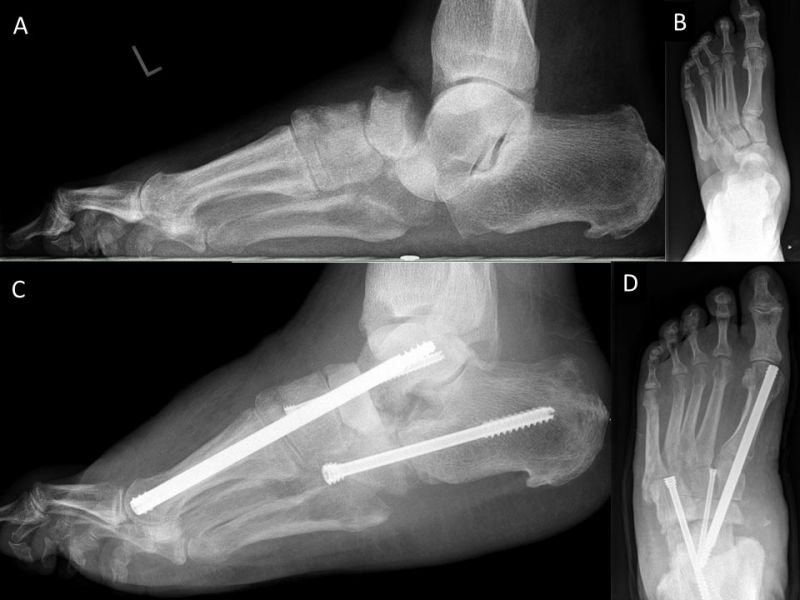

Als Folge der diabetesbedingten Neuropathie kann es zu dem sogenannten Charcotfuß kommen. Bei dieser Komplikation der Diabeteserkrankung kommt es häufig zu einer Zerstörung der Fußwurzelgelenke und -knochen. Dabei springen die Knochen aus den Gelenken (Luxation) und brechen (Fraktur). Der Fuß verliert an Halt und das Fußgewölbe kann zur Fußsohle durchbrechen (Plattfuß). Hierbei treten Druckstellen durch überstehende Knochenfragmente an der Fußsohle auf, die dann zu Hautschäden führen. Sollten hier konservative Therapiemaßnahmen (Polsterung/Schuhzurichtung) versagen, ist eine operative Korrektur angezeigt. Dabei werden die Knochen mittels Platten und langen Schrauben stabilisiert.

Zum Lesen der Bildbeschreibung und Vollansicht bitte Bild anklicken. Fotos: Alexander Mehlhorn

Eine weiterer typischer Verlauf eines Charcot Fußes betrifft die Zerstörung der Bänder und des oberen Sprunggelenks. Der Fuß knickt dabei nach innen, manchmal auch nach außen weg. In Schuhen kommt es meist zu Druckstellen im Bereich des Knöchels. Teilweise ist das Sprunggelenk ist so instabil, dass Laufen nicht mehr möglich ist. Oft sind hier die Möglichkeiten einer konservativen Therapie mit Polsterung/Schuhversorgung nicht mehr ausreichend. Kann der Fuß von außen nicht mehr ausreichend stabilisiert werden, ist eine operative Stabilisierung der abgekippten Gelenke mit Platten und Schrauben notwendig um wieder einen belastbaren Fuß zu erreichen.